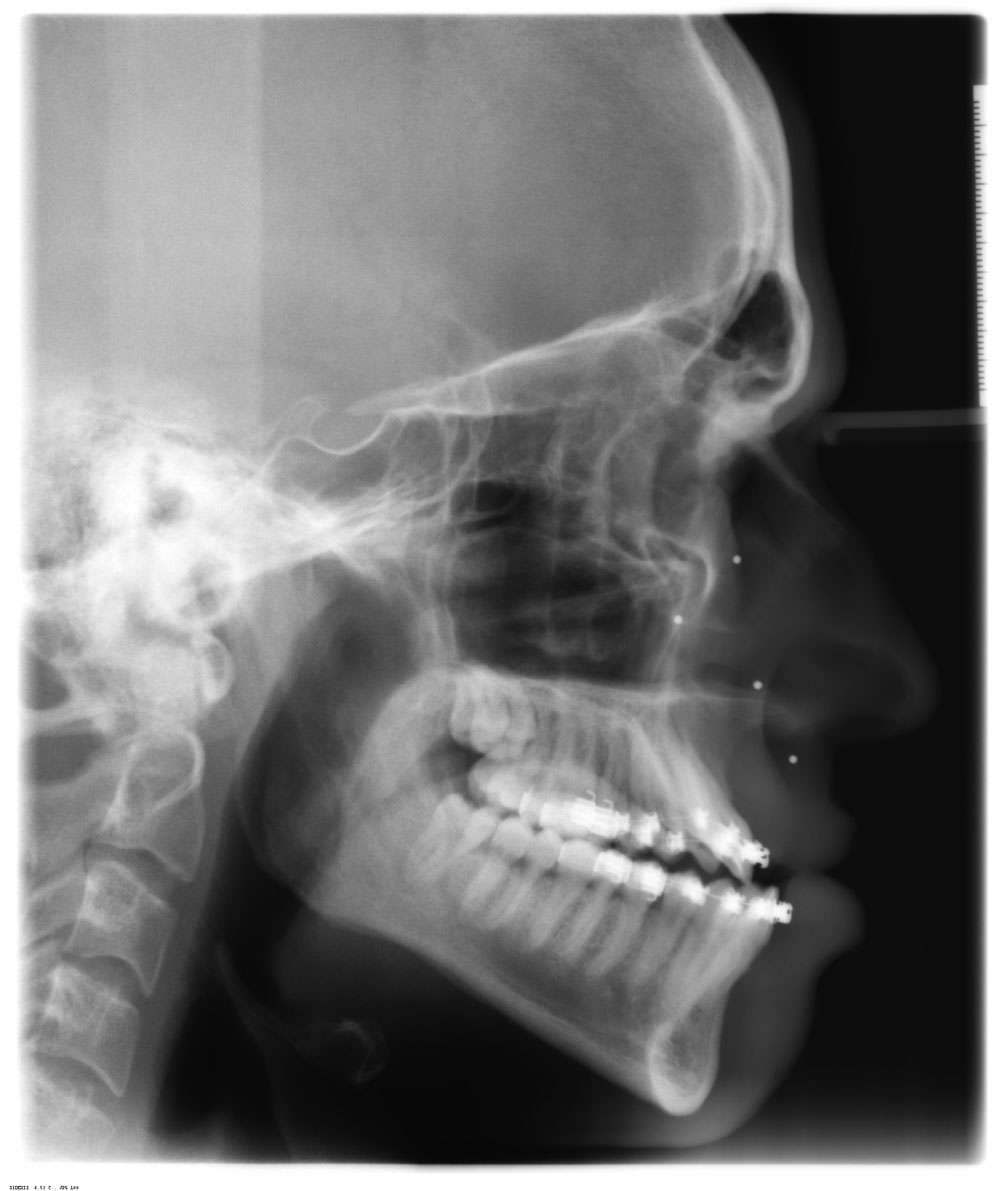

Before and After XRay of a patient I treated with TipEdge Plus braces

Before and After XRay of a patient I treated with TipEdge Plus braces Can You Do X Ray With Braces They provide detailed information about the position and condition of the teeth and jaw, allowing the orthodontist to develop a customized treatment plan. Book an appointment with your general dentist. The bos provides a transfer form. Find out about braces and orthodontics, including how much they cost on the nhs or privately, and how to care for your teeth while. Can You Do X Ray With Braces.